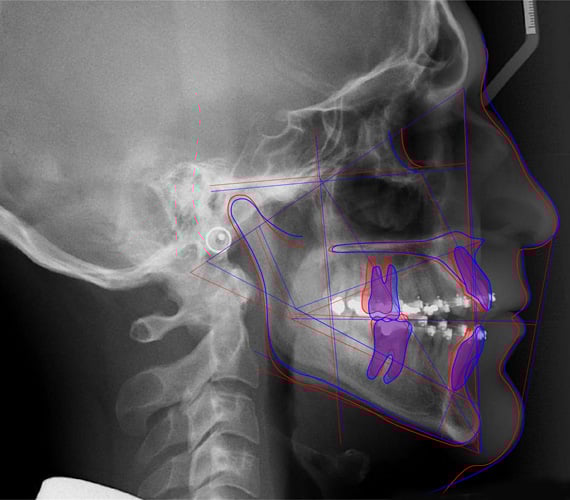

Romexis Cephalometric Analysis offers easy-to-use tools that make analysing images both quick and efficient. The software's automatic tracing feature places the points and soft tissue silhouettes on a cephalometric image in a matter of seconds – leaving you more time to interpret the results of the analysis.

The Romexis Cephalometric Analysis software module allows you to simulate surgical and orthodontic treatments by creating a cephalometric visual treatment objective (VTO) with a prediction image.